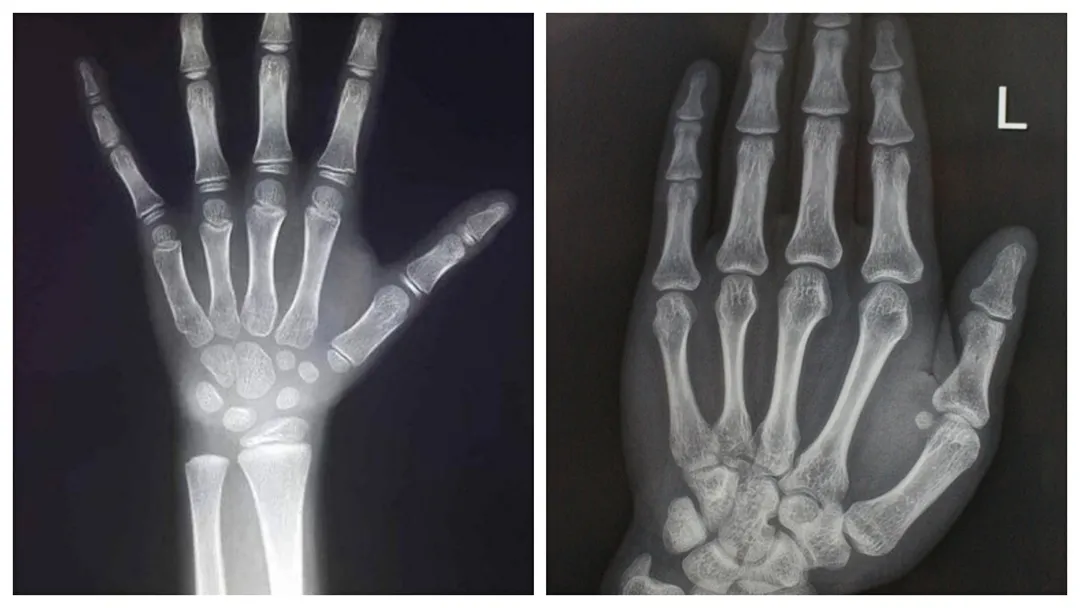

左图:骨龄未闭合 右图:骨龄闭合